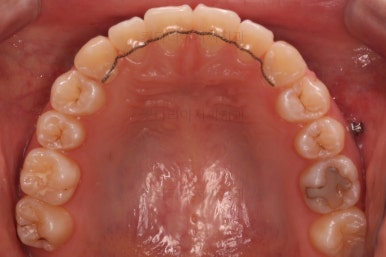

교합도 안정되는 것을 확인했고, 치열도 만족할 수준으로 디테일한 정리를 해줬어요.

왼쪽이 치료 초기의 교합 모습, 오른쪽이 치료 마무리 시점의 교합입니다.

빈틈이 많았던 교합이 많이 개선된 것이 보이시죠?

이러한 이유 때문에 전체교정이 필요했답니다.

약간의 정리 후, 마무리를 하였습니다.

총 치료기간은 13개월이 걸렸네요.